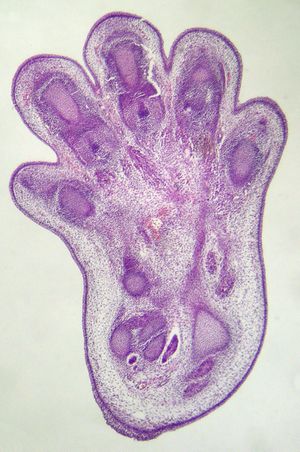

In contrast to necrosis, which is a form of traumatic cell death that results from acute cellular injury, apoptosis is a highly regulated and controlled process that confers advantages during an organism's life cycle. For example, the separation of fingers and toes in a developing human embryo occurs because cells between the digits undergo apoptosis. Unlike necrosis, apoptosis produces cell fragments called apoptotic bodies that phagocytes are able to engulf and remove before the contents of the cell can spill out onto surrounding cells and cause damage to them.[5]

The frog Xenopus laevis serves as an ideal model system for the study of the mechanisms of apoptosis. In fact, iodine and thyroxine also stimulate the spectacular apoptosis of the cells of the larval gills, tail and fins in amphibian's metamorphosis, and stimulate the evolution of their nervous system transforming the aquatic, vegetarian tadpole into the terrestrial, carnivorous frog.[45][46][47][48]